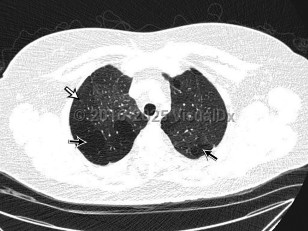

Imaging Studies image of Bronchiolitis obliterans - imageId=8347118. Click to open in gallery.  caption: '<span>Axial 0.90mm slice thickness  non-contrast CT image of the chest viewed in lung windows in the upper  chest. Axial CT image of the chest demonstrates mosaic attenuation  throughout both lungs, with geographic areas of decreased attenuation  (straight black arrows) and decreased vascularity (straight white  arrow).</span>'

Axial 0.90mm slice thickness non-contrast CT image of the chest viewed in lung windows in the upper chest. Axial CT image of the chest demonstrates mosaic attenuation throughout both lungs, with geographic areas of decreased attenuation (straight black arrows) and decreased vascularity (straight white arrow).